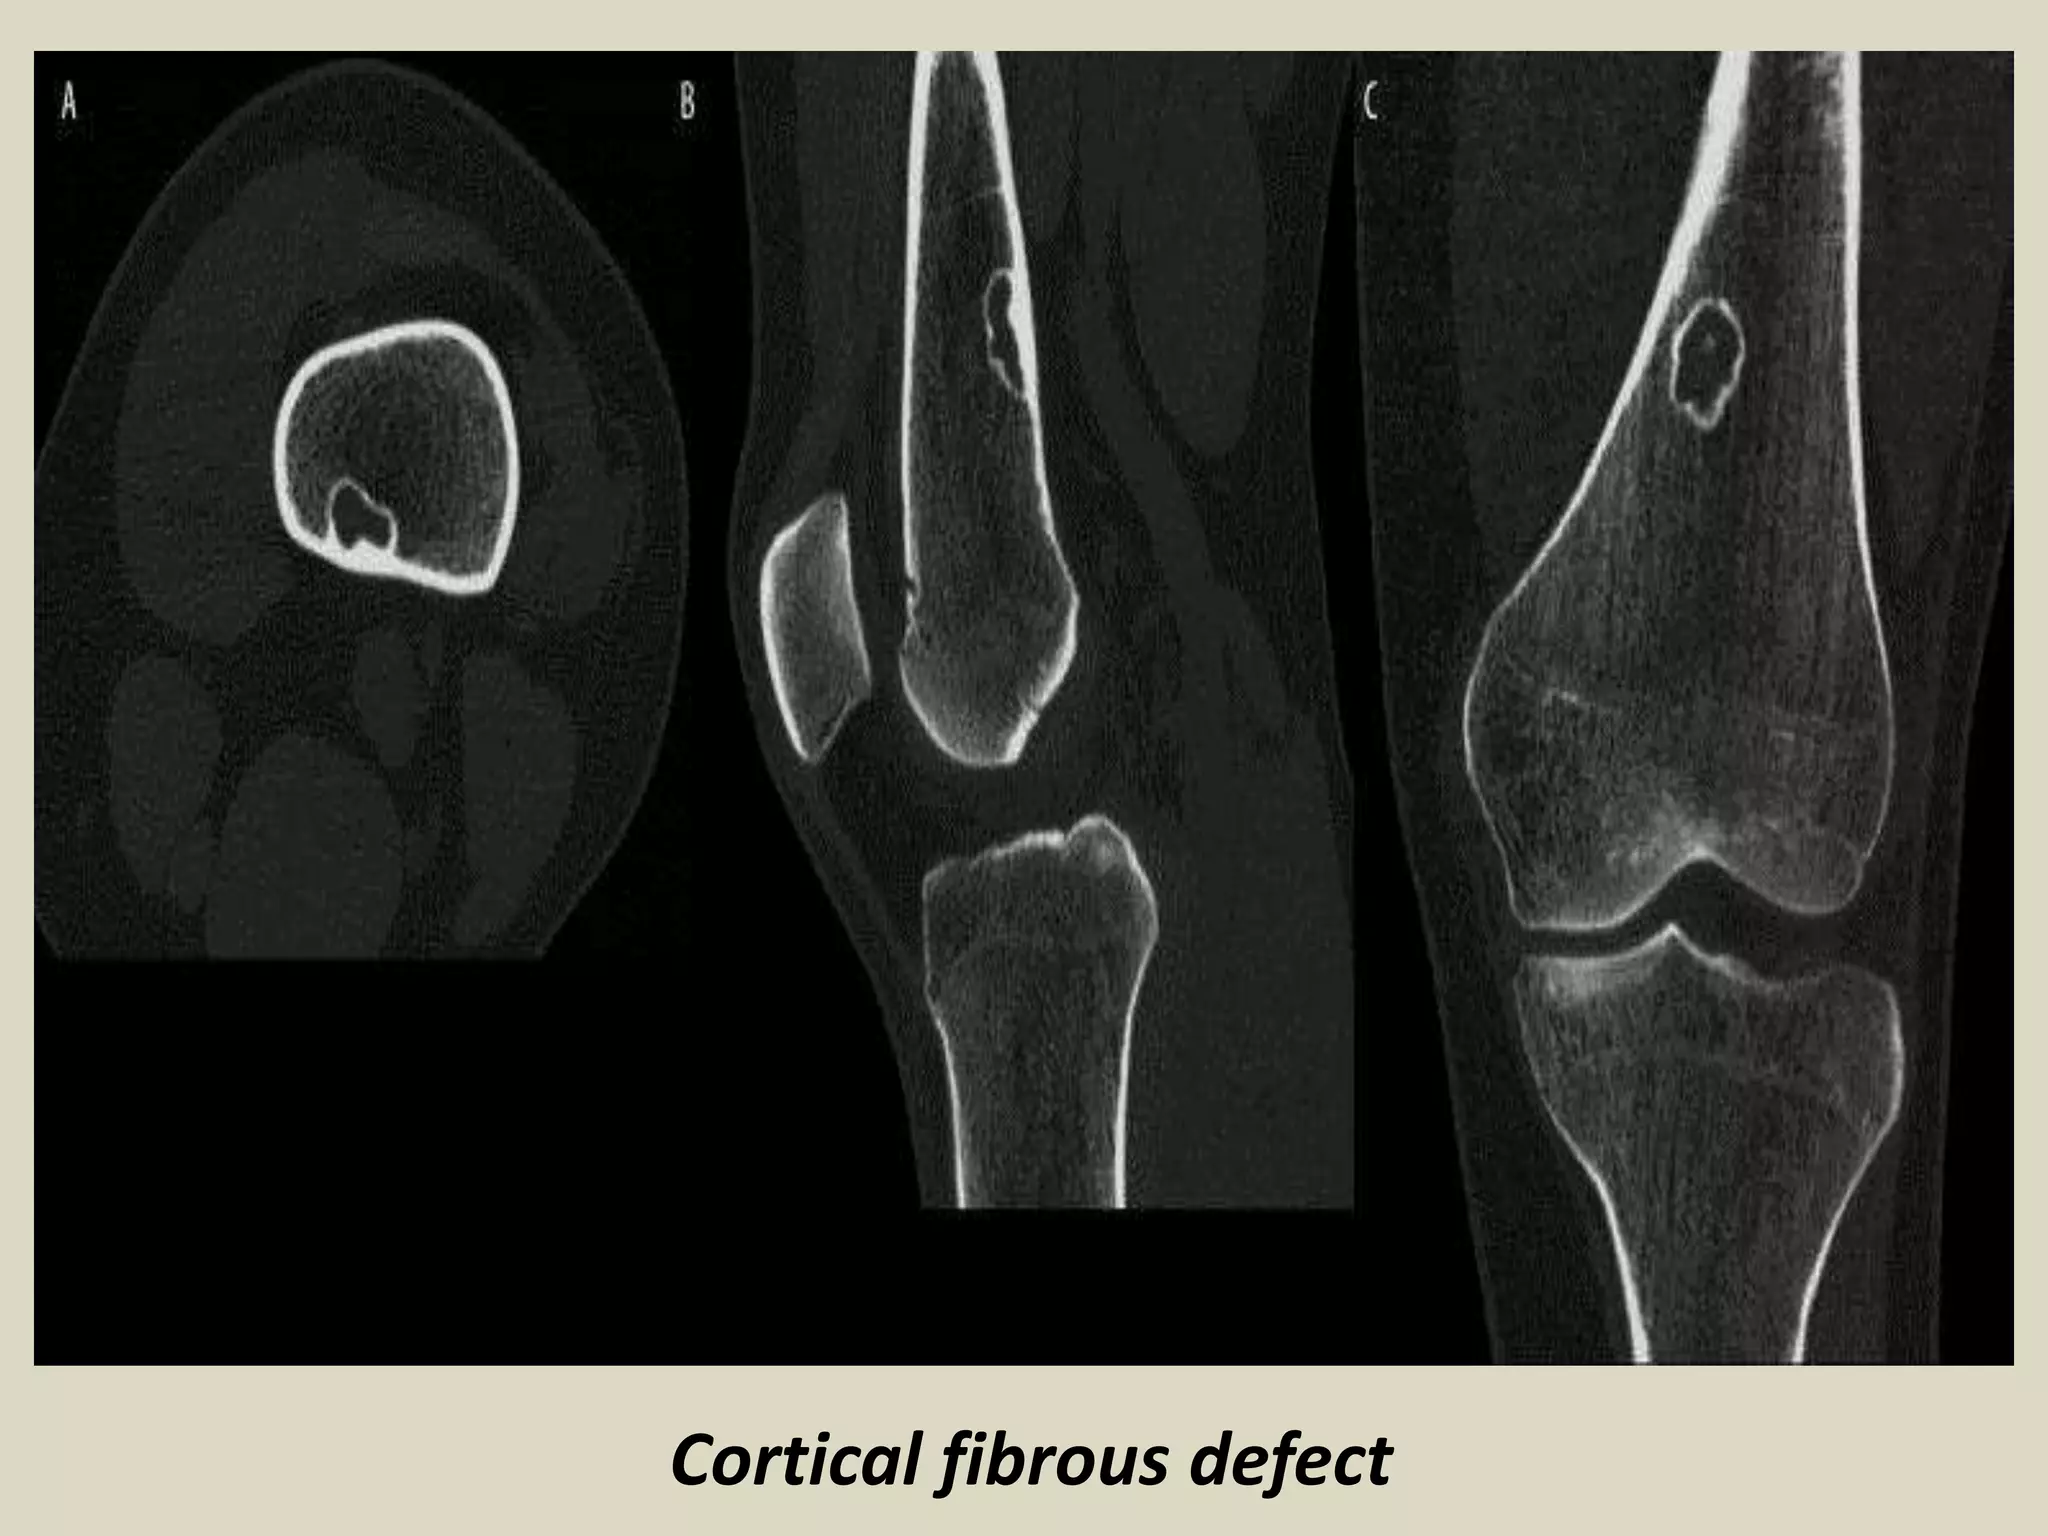

FIBROUS CORTICAL DEFECT/NON-OSSIFYING FIBROMA

Definition:

- Benign lesion of bone composed of spindle-shaped fibroblasts, arranged in a storiform

pattern, with a variable admixture of multinucleated osteoclast-like giant cells.

- Epidemiology:

- Patient have ranged in age from 6 to 74 years old. 30-40% in children.

- An average age of 4 years 54% of boys and 22% of girls, had a lesion involving the

cortex, and most regressed spontaneously over a period of approximately 2.5 years.

Site of involvement:

- Approximately 40% of NOF occur in the long bones, with distal femur, distal and proximal

tibia most frequently involved.

- As many as 25% of cases involve the pelvic bone, in particular the ilium.

Clinical findings:

- Majority of NOF cases are asymptomatic, and are an incidental discovery on X-rays

performed for other reasons.

- Larger lesion may cause pain that is probably secondary to microfractures or obvious

pathologic fracture.

- Most pathologic fractures develop through lesions that involve more than 50% of the

diameter of the bone.

-The vast majority of NOF are single, although they are multiple in 8% of cases.

- Multiple NOF may be associated with syndromes such as neurofibromatosis.

Imaging:

- Eccentric, lytic lesions centered within the metaphyseal cortex and adjacent medullary cavity

- of long tubular bones.

- Well demarcated with sclerotic margins and frequently harbor internal trabeculation.

FIBROUS TUMORS

Cortical fibrous defect

Fibrous cortical defect.